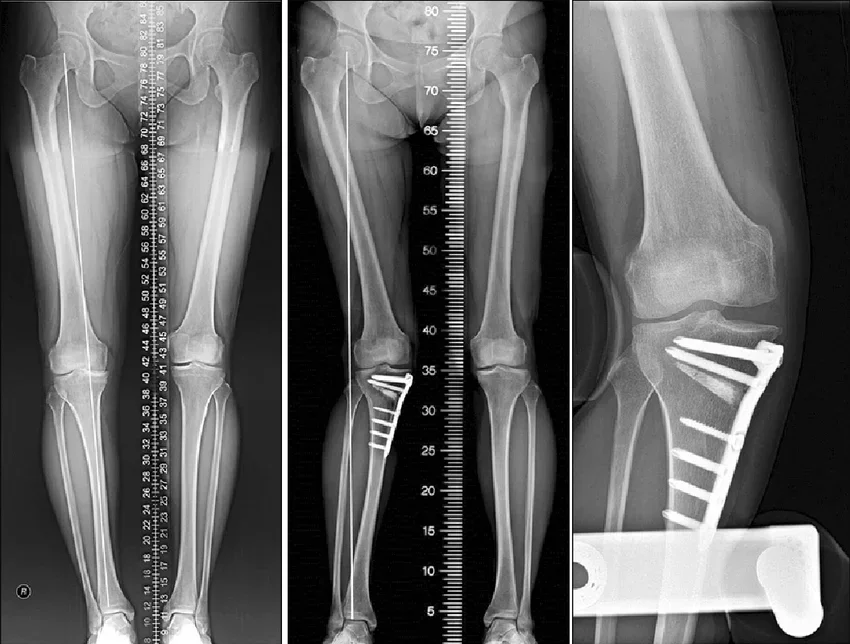

How Dr. Siddharth Performs Tibial Osteotomy in Nagpur

Here’s what happens step by step:

- The surgery is done under anaesthesia.

- A small cut is made near the upper tibia (shinbone).

- The bone is carefully opened or closed to correct the angle.

- A small plate and screws hold the bone in the new position.

- The corrected angle allows weight to spread evenly across the joint.

Knee alignment surgery/HTO is a minimally invasive procedure that takes about 1–2 hours. And most patients start walking with support within a few days.

During this time, Dr. Jain’s team supports you with exercise plans, diet guidance, and follow-up X-rays to ensure your knee heals perfectly.